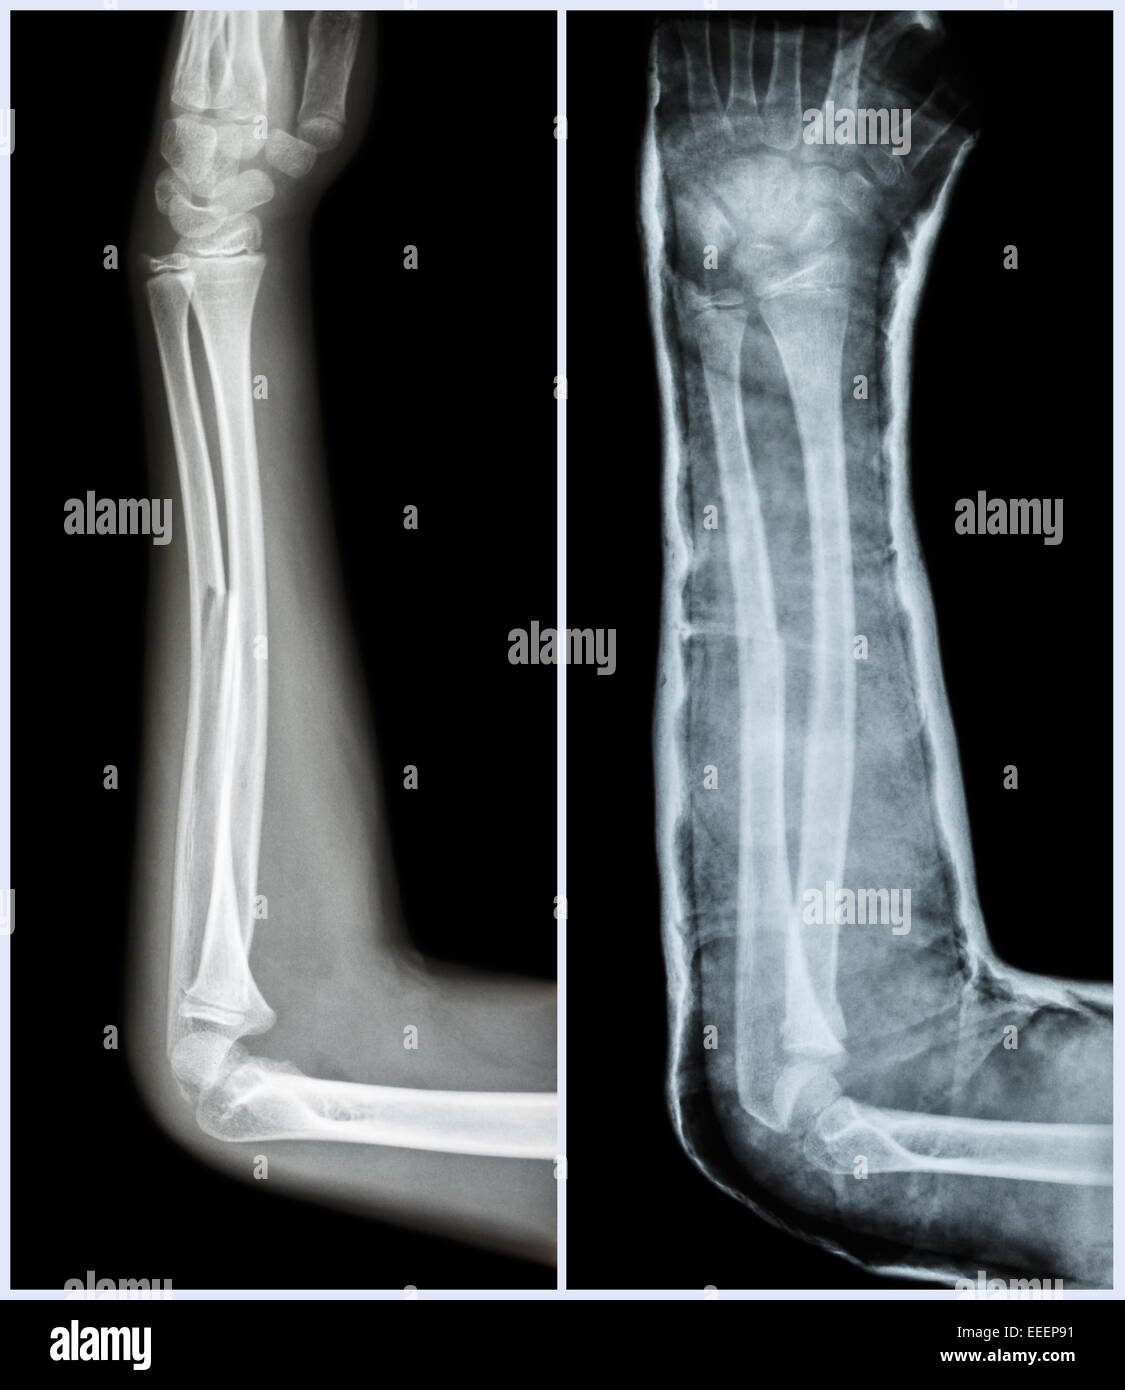

From www.alamy.com

Fracture shaft of ulnar bone ( forearm bone ) ( Left pretreatment Splint For Ulnar Shaft Fracture    if initial imaging findings are negative and suspicion of fracture remains, splinting and repeat radiography in seven to 14 days should be performed. Determine the appropriate evaluation of radius and. They most often result from a direct trauma to the ulna as the.   the epidemiology, clinical anatomy, assessment, diagnosis, and nonoperative management of midshaft.   distal ulnar fracture. Splint For Ulnar Shaft Fracture.